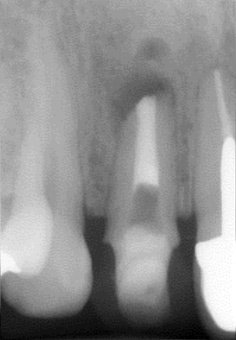

CTで見たときも悪い黒い影は見当たりません。黄色の矢印は骨です。しかし、赤の矢印の部分の根の先端は骨から少し出てるような感じがします。

これだけでは、確定的な診断は出来ませんが、「フェネストレーション」の疑いはかなり高いです。

治療前

まずは以前に詰めてある根管充填剤を全て除去し徹底的に根管内をきれいにしMTAセメントで埋めなおします。